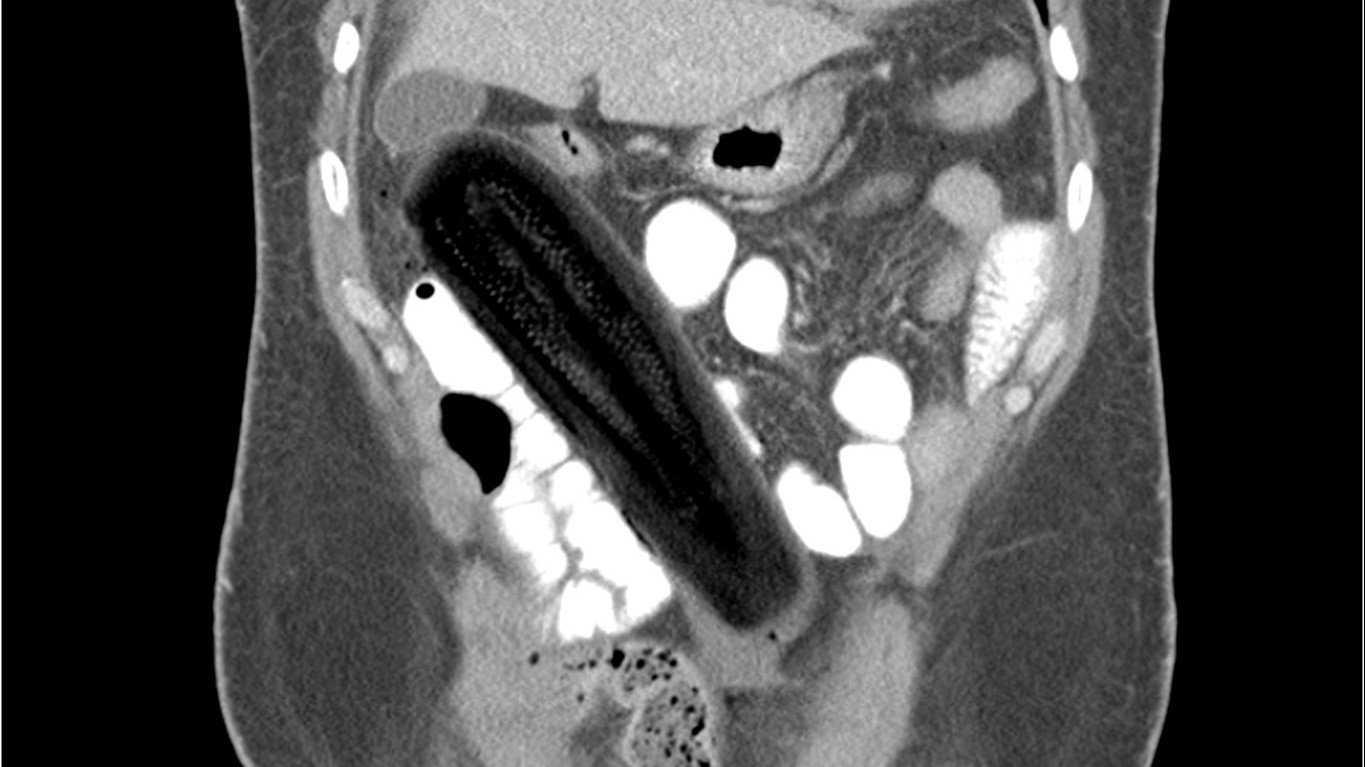

X-ray yeterince bilgi vermediği için CT çekilmesine karar verilen hastanın sorununun peritoneal boşluk içerisine sıkışmış 19 santimetrelik bir kabak olduğu anlaşılmıştır. Hastanın anal yollarla kabağı oraya sokacak kadar sert bir şekilde ittiği, anüs açıklığını yırtarak peritoneal boşluğa kadar ulaştığı öğrenilmiştir. Aşağıda CT sonucu görülebilir: